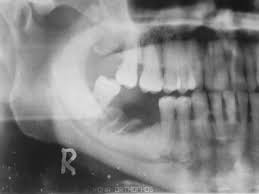

Osteonecrosis de la mandíbula relacionada con la medicación: análisis de la gama de fármacos implicados de la base de datos australiana de notificaciones de eventos adversos

Este estudio contribuye a la escasa pero creciente literatura que asocia un número creciente de fármacos con osteonecrosis de la mandíbula relacionada con la medicación (ONMRM)  y subraya la importancia de considerar todos los fármacos posibles que elevan el riesgo de ONMRM de un paciente. Br J Clin Pharmacol, junio de 2021